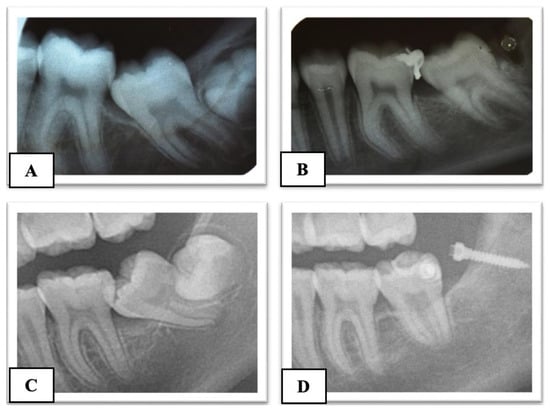

The angulation of the lower permanent second molar was measured on the panoramic radiograph as described by Evans [4]. Two lines were drawn connecting the tips of the cusps of the first and second molars; from these, two perpendicular lines representing the long axes of the teeth were traced. The angle formed between the long axes of the first and second molars was measured, representing the impaction angle of the second molar.

The impacted depth was measured, as described by Fu et al. [17], as the vertical distance from the distal marginal ridge of the first molar to the mesial marginal ridge of the impacted MM2 (Figure 1).

Figure 1. Orthopanoramic evaluation of angle (A) and depth (B) of impacted MM2.